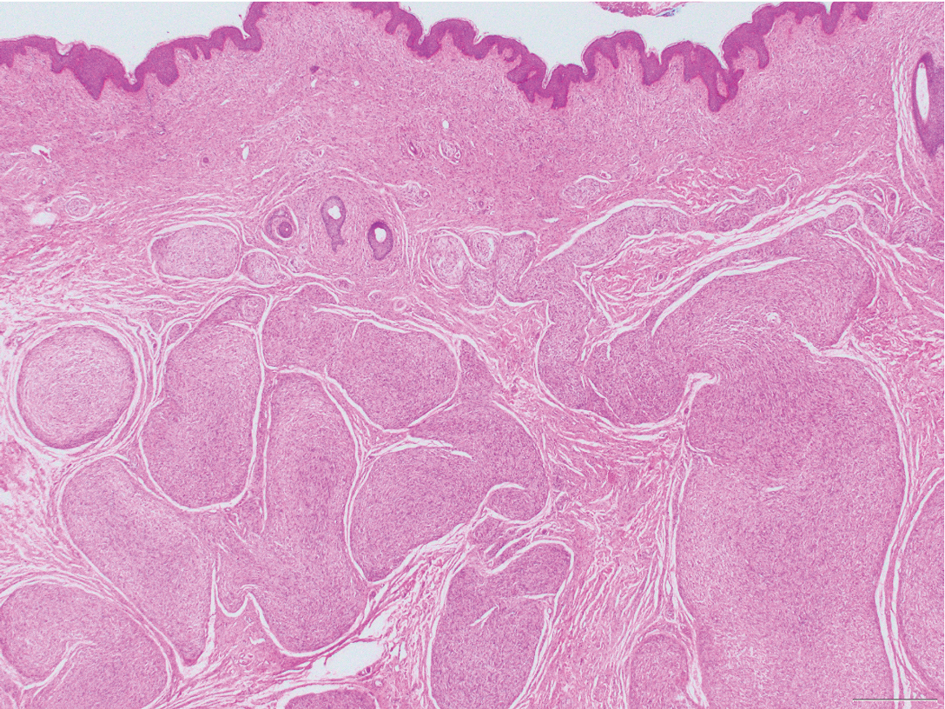

Schwannomas are encapsulated tumors that originate from the outer sheath of peripheral nerves, usually positioned eccentrically to the nerve fibers. Schwannomas are characterized by Antoni A and Antoni B areas, which usually are absent in PEN. Antoni A areas are composed of compact spindle cells arranged in palisades with Verocay bodies, while Antoni B areas are more loosely arranged and have a myxoid background (Figure 3).8,9 Schwannomas stain positive for S-100 and often show degenerative changes such as cystic degeneration or calcification, particularly in larger lesions.8,9 Plexiform schwannoma is a rare variant of schwannoma, and while it carries a substantial risk for local recurrence with rates as high as 50%, it has not been shown to possess malignant or metastatic potential.10 Unlike PEN, schwannomas have a consistent capsule but share S-100 positivity with PEN. Verocay bodies occasionally can be observed in PENs, with studies reporting their presence in 20% to 36% of cases.7,11,12 Additionally, some schwannomas may exhibit few Verocay bodies or poorly developed forms, which can make histopathologic distinction more challenging.7,11,12

FIGURE 3. Schwannoma with red arrow pointing to myxoid Antoni B area under the capsule and blue arrow pointing to cellular Antoni A area (H&E, original magnification ×100).